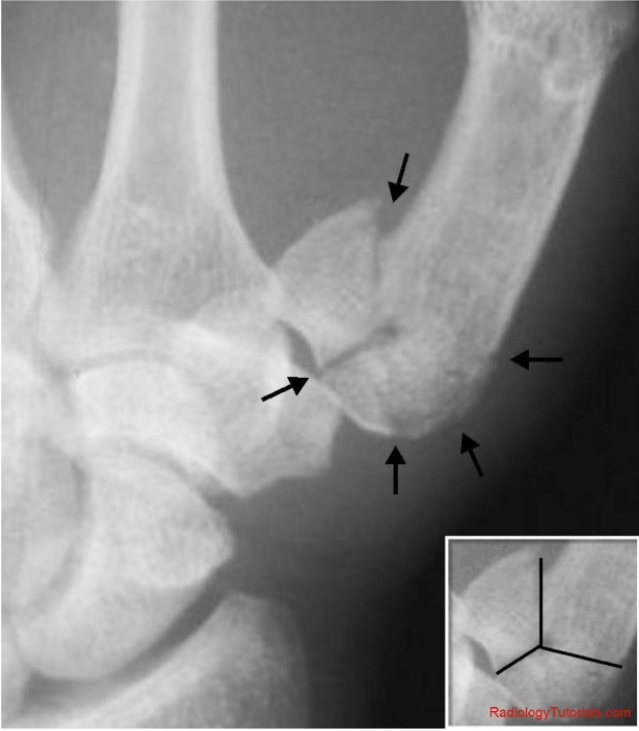

Que fractura se presenta en esta imagen

Colles

que clasficacion es esta?

Frymann

IZQUIERDA→ NUMEROS NONES INVOLUCRA SOLO AL RADIO

A. 1 → EXTRARTICULAR

B. 3→ INTRARRTICULAR

C. 5→ ARTICULACION RADIO CUBITAL DISTAL

D. 7→ AMBAS ARTICULACIONES AFECTADAS